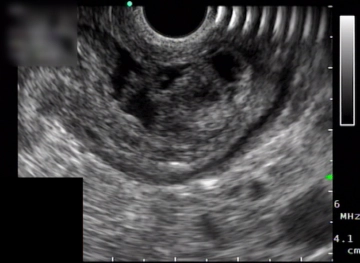

Endosonográficamente corresponde este tumor a una lesión ocupante de espacio eco-inhomogénea de 26 × 12 mm de tamaño dentro de la pared gástrica. -